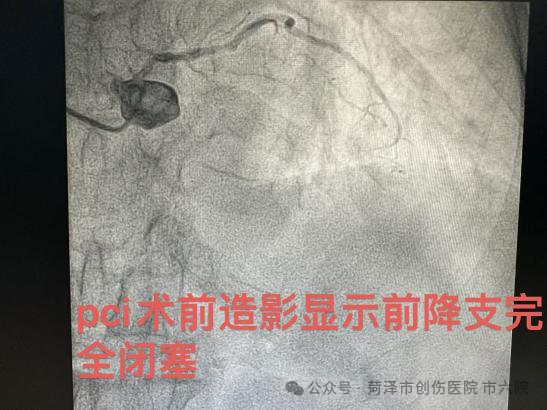

该患者因频繁胸痛于我院心内科治疗,张吉宏主任为其造影后确诊为三支病变,左主干病变,前降支闭塞,对角支次闭塞,病情十分危重。考虑到患者年龄较大,介入风险极高,建议家属行心外科搭桥手术。患者及其家属考虑到搭桥手术创伤较大,术后恢复较慢,坚决拒绝搭桥手术治疗,随稳定后出院。出院不到一周时间,患者再次出现严重胸痛,不能自主活动。出于对张主任以及我院的信任,家属最终决定在我院进行介入手术治疗。考虑到患者年事已高,身体机能较弱,同时合并多种基础疾病,手术治疗面临着导丝通过困难、术后并发症风险高等多重挑战。面对这一棘手病例,恰逢联勤保障部队第九六〇医院专家晋群主任于我院帮扶并给予会诊,晋主任第一时间查看患者和翻阅病历资料,制定了详尽的个性化治疗策略和应急预案。并决定在主动脉内球囊反搏(IABP)的支持下,对该患者进行冠脉介入治疗手术。为确保手术顺利进行,张吉宏主任提前通知团队进行主动脉内球囊反搏(IABP)业务学习,做好充足的术前准备,为手术保驾护航。

10日下午,联勤保障部队第九六〇医院介入诊疗团队抵达我院,在专家团队的加持下,患者经过两小时的介入治疗,手术获得圆满成功,分别于前降支置入支架三枚,回旋支置入支架一枚,血管内超声显示支架贴壁良好,冠脉三级血流恢复,症状完全缓解,术中患者全程意识清醒,生命体征平稳,无明显不适。“不用开胸搭桥,多受罪了!,谢谢你们!”得知手术顺利完成,患者家属十分感激地说到。